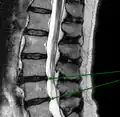

L'imagerie par résonance magnétique peut montrer la hernie, le canal vertébral, les nerfs, les tissus environnants. Les tissus mous sont les mieux analysés par cet examen qui est le plus performant pour le diagnostic de hernie discale. Les images pondérées en T2 montrent clairement la hernie.

IRM lombosacrée sagittale montrant une hernie discale de niveau L4-L5.